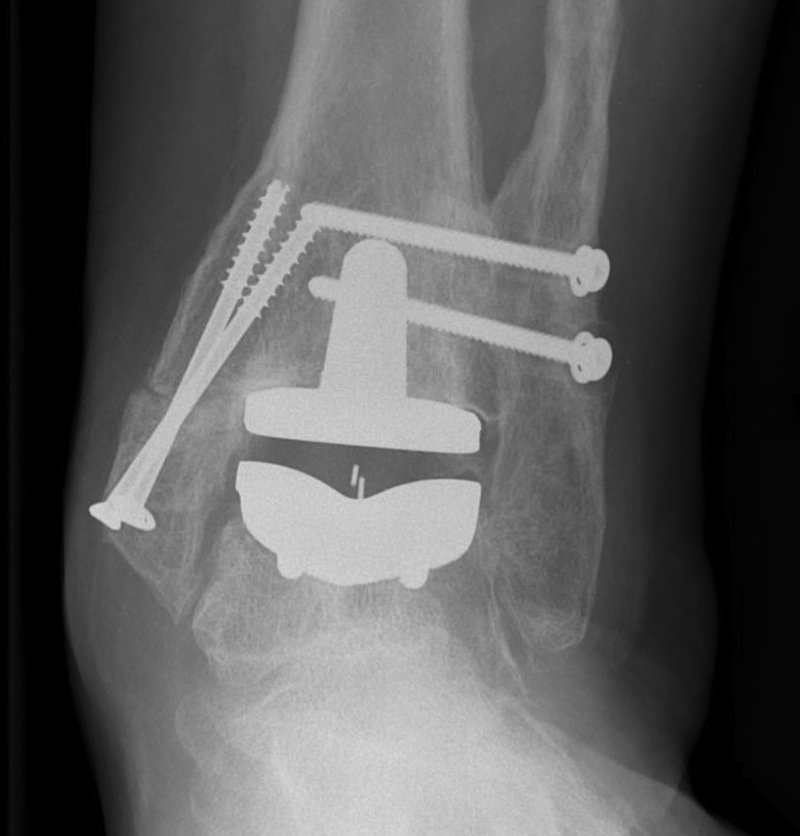

Infinity implant STAR implant Inbone

Agility Salto Tolaris Trabecular metal

B. Lateral approach and fibular osteotomy

Zimmer Biomet Trabecular Metal PDF